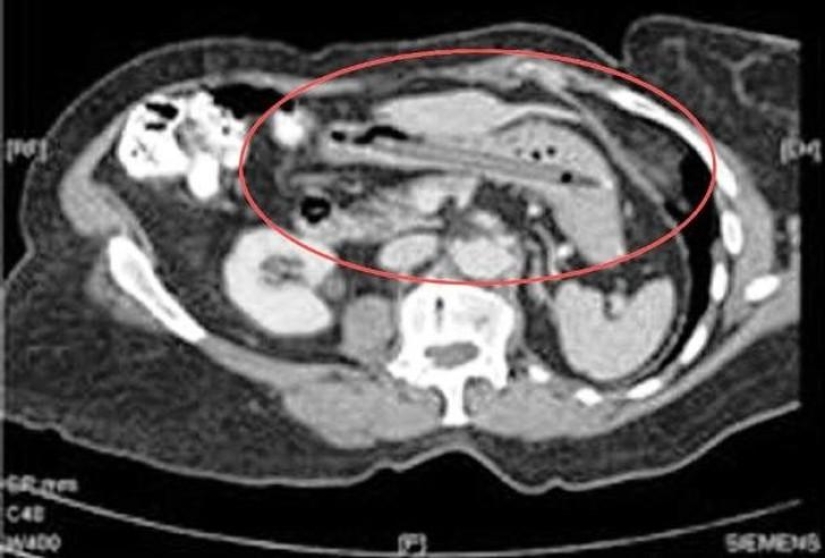

Huge ball of wool.